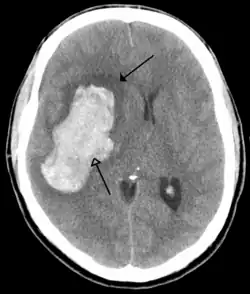

CT scan of an intraparenchymal bleed (bottom arrow) with surrounding edema (top arrow)

There are two main types of hemorrhagic stroke:[30][31]

The above two main types of hemorrhagic stroke are also two different forms of intracranial hemorrhage, which is the accumulation of blood anywhere within the cranial vault; but the other forms of intracranial hemorrhage, such as epidural hematoma (bleeding between the skull and the dura mater, which is the thick outermost layer of the meninges that surround the brain) and subdural hematoma (bleeding in the subdural space), are not considered "hemorrhagic stroke".[32]

Hemorrhagic stroke may occur on the background of alterations to the blood vessels in the brain, such as cerebral amyloid angiopathy, cerebral arteriovenous malformation and an intracranial aneurysm, which can cause intraparenchymal or subarachnoid hemorrhage.[33]